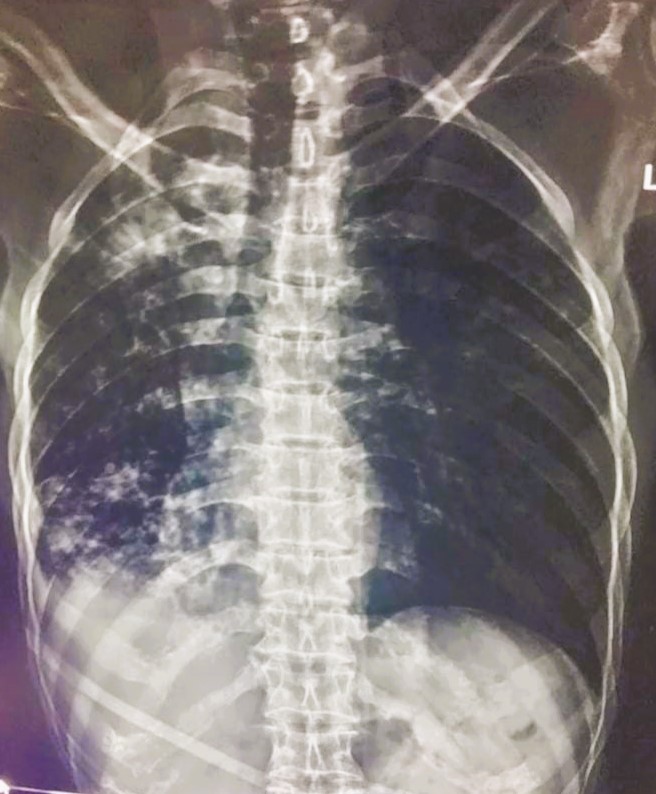

| 192 | IGGMC, Nagpur, Nagpur | P2 | 29-4280 | SONALI CHORSIYA | Consent taken on Paper | 30 Yrs. |

Provisional Diag : DISSEMINATED TB?

Final Diag : DISSEMINATED TB (MICROBIOLOGICALLY CONFIRMED PTB +MILLIARY TB) WITH ATYPICAL PNEUMONIA |

Mix (TB and Non-TB) | BILATERAL INFILTRATION/BILATERAL LOWER ZONE RETICULAR SHADOWS | Abnormality visible on x-ray |